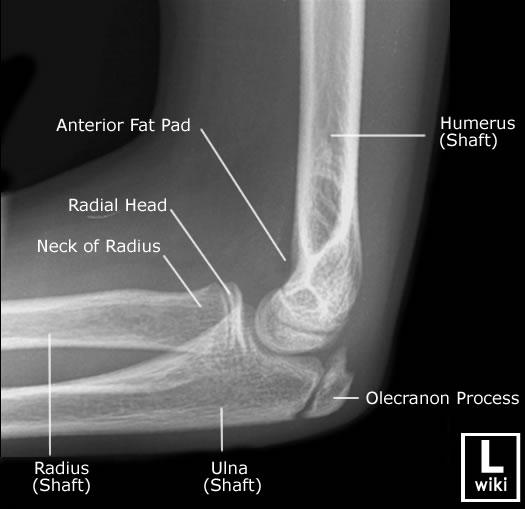

| Articulación sana de un niño. Créditos: Wikiradiography. |